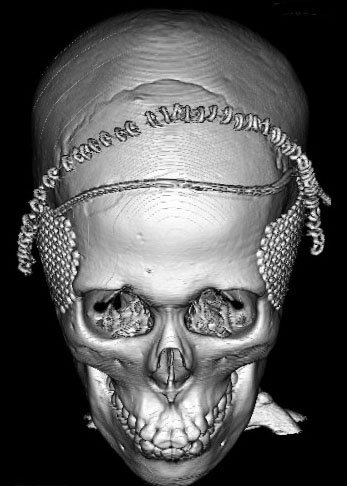

全脳照射後の頭蓋骨の部分的発育不全

2歳くらいで全脳照射を受けた子どもが15歳になりました。前頭骨だけの発育が悪くて額の間がとても狭くて,コメカミの凹みが目立つようになりました。両側の側頭部にチタンプレートを入れて額を広くして頭蓋形成をして,見栄えはとても良くなりました。このような手術を整容的頭蓋形成術といいます。